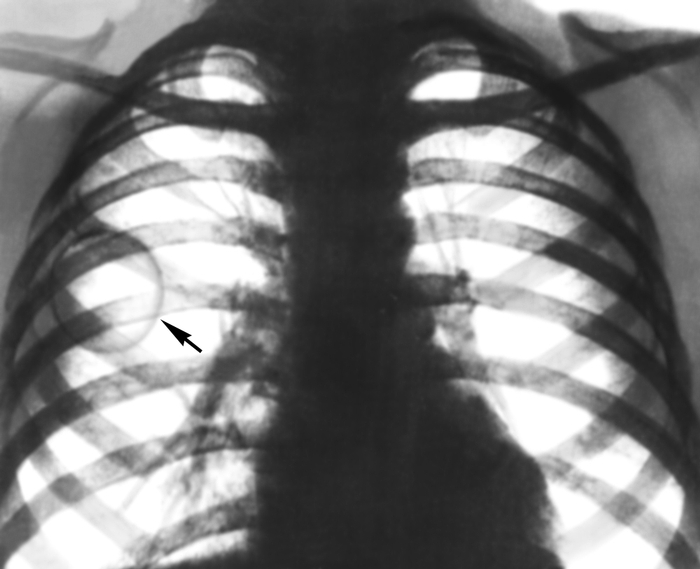

Рентгеновские снимки при врожденной эмфиземе легкого

Раздел: Визуальные уроки